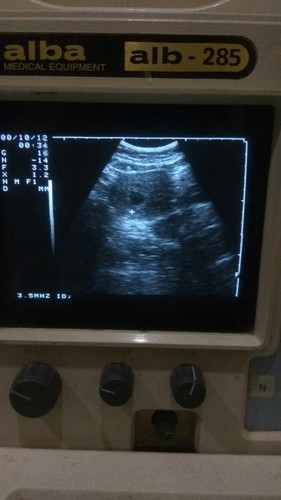

Selamat pagi Bunda, HPLku 16 Oktober dan hari ini sudah lewat 2hari. Sekarang masih ngerasain kontraksi palsu itu pun jarang sama nyeri tulang pinggul aja, segala induksi alami udah dilakuin. Mulai dari jjp jjs, power walk 30menit, squat, main gymball, hb dikeluarin di dalem setiap hari, makan nanas, kiwi, kurma, sampai treatment induksi alami pake moxa dan akupunktur tapi belum juga ada kontraksi asli. Terakhir USG pas UK 40mg kata dokter semua masih normal dan ketuban cukup jadi masih bisa ditunggu maksimal 1minggu lagi kalo belum lahir juga harus diinduksi. Pengen relaks tapi kadang khawatir juga :( Bunda di sini ada yang punya pengalaman persalinan normal pervaginam lewat HPL gak? Apa kalo udah lewat HPL kemungkinan besar harus diinduksi? Mohon doa dan sharingnya dong, Bund 😭 #seriusnanya #bantusharing #ingintahu #pleasehelp #firstbaby